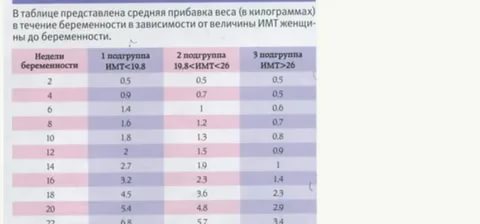

29 неделя беременности: сколько это месяцев и чего ожидать?